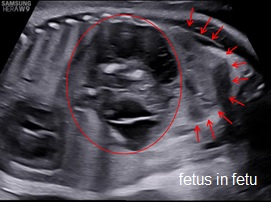

Fetus in Fetu (FIF) là bất thường rất hiếm gặp của song thai một trứng, trong đó một thai không trưởng thành sống ký sinh trong cơ thể của thai bình thường